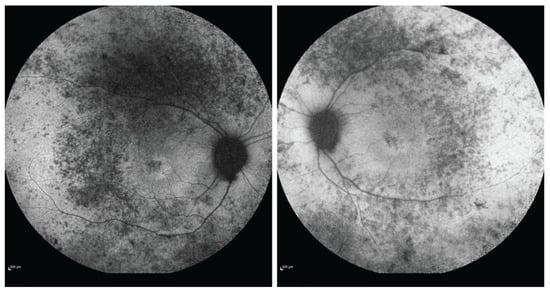

| Paine et al., 2019 [4] individual 9 | c.2021C > T p.(Thr674Met) heterozygous | C-terminal | De novo | Male | 10 months | Infancy | Epilepsy, developmental delay, myopathy, peripheral neuropathy, hypertrophic calves, ataxic gait, unable to walk | Sensorineural hearing loss, retinopathy, complete vision loss, contractures | Normal | Febrile seizure | At age 34 wheelchair-bound, blind, deaf |

| Drackley et al., 2024 [5] | c.2033A > G p.(Glu678Gly) heterozygous | C-terminal | De novo | Female | Birth | 15 years | Hypotonia, motor delay, sensorimotor axonal neuropathy, myopathy, ADHD | Bilateral sensorineural hearing loss, retinitis pigmentosa, premature adrenarche, primary ovarian insufficiency | n/a | Bilateral sensorineural hearing loss | n/a |

| Present case | c.2032G>A, p.(Glu678Lys) heterozygous | C-terminal | De novo | Female | Birth | 36 years | Facial palsy, swallowing difficulties, nasal speech, myopathy, flaccid tetraparesis | Sensorineural deafness, retinitis pigmentosa, primary ovarian deficiency | Normal | Sensorineural hearing loss | Deaf, wheelchair-bound |